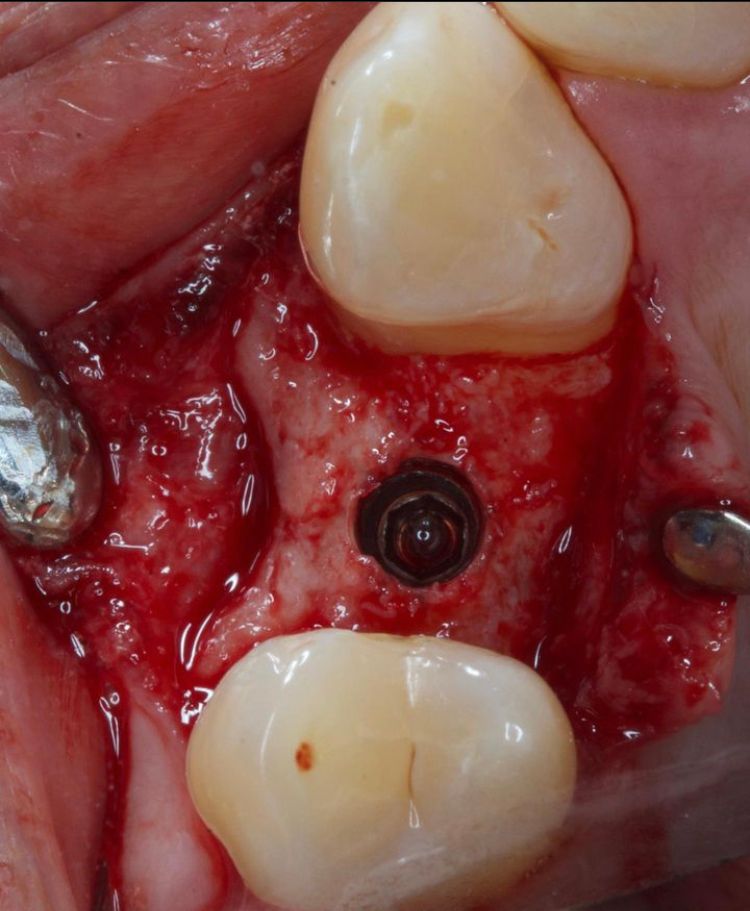

¿Que es un Implante Dental?

- Es un aditamento con forma de tornillo elaborado de titanio o de zirconio, que se inserta en el hueso a través de una pequeña cirugía, hasta que se osteointegre con el hueso y se coloque un provisional y posteriormente una corona definitiva.

-La ventaja de los Implantes Dentales es que sustituyen a los dientes o muelas perdidos sin que se tenga que desgastar los dientes adyacentes para un puente fijo.